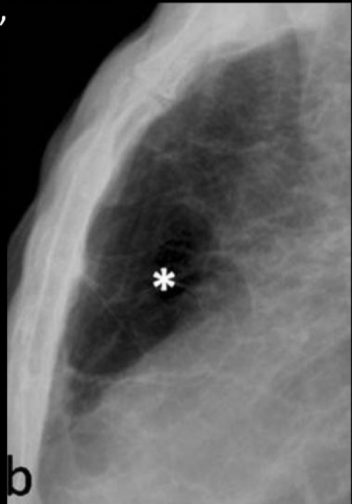

Q

Esta lesión es característica de enfisema pulmonar, ¿cuál es y por qué piensas que es esta?

A

Bullas, paredes delgadas e irregulares